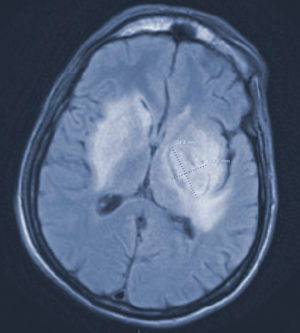

Read more about the case of a 71-year-old man who was admitted after presenting with cold-like symptoms for 3 weeks.

Clinicians review a patient case including diagnosis, treatment, and follow-up.